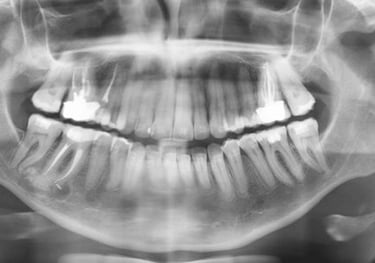

RADIOGRAFIA PANORÂMICA